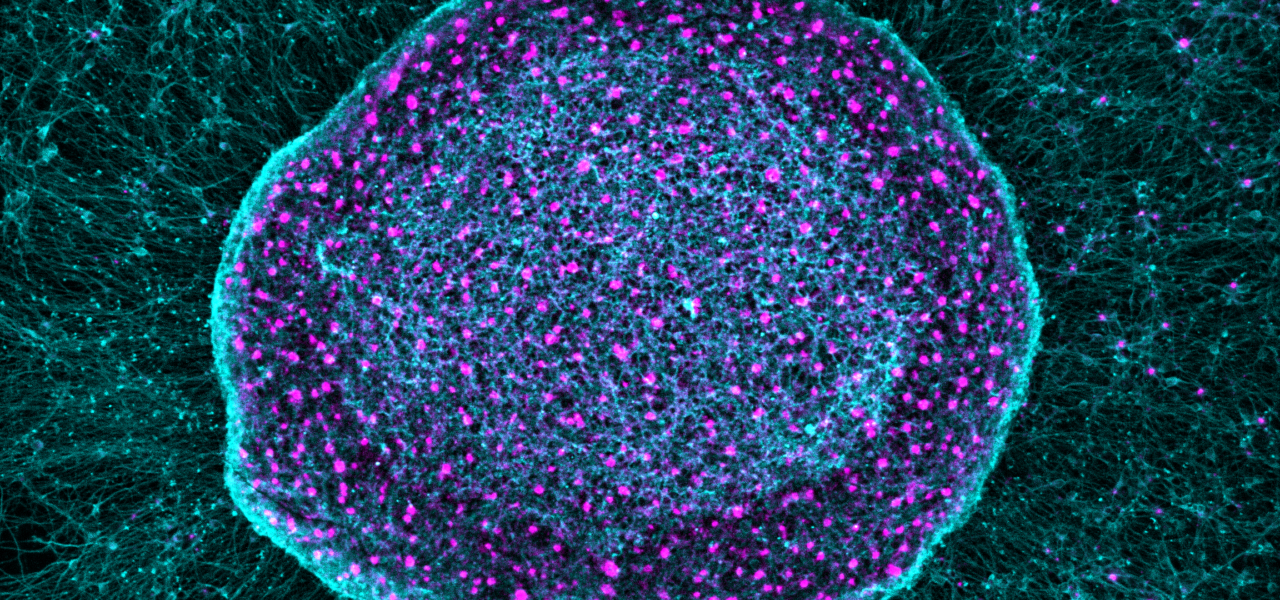

SN101 challenges conventional pain management strategies by using mature, iPSC-derived peripheral pain-sensing neurons (nociceptors) as a therapeutic tool rather than a target.

Rather than transmitting pain signals to the brain, SN101 cells sequester inflammatory pain mediators locally within the joint. The cells also secrete mechanistically validated regenerative factors, creating an environment that supports healthier cartilage and bone remodeling.